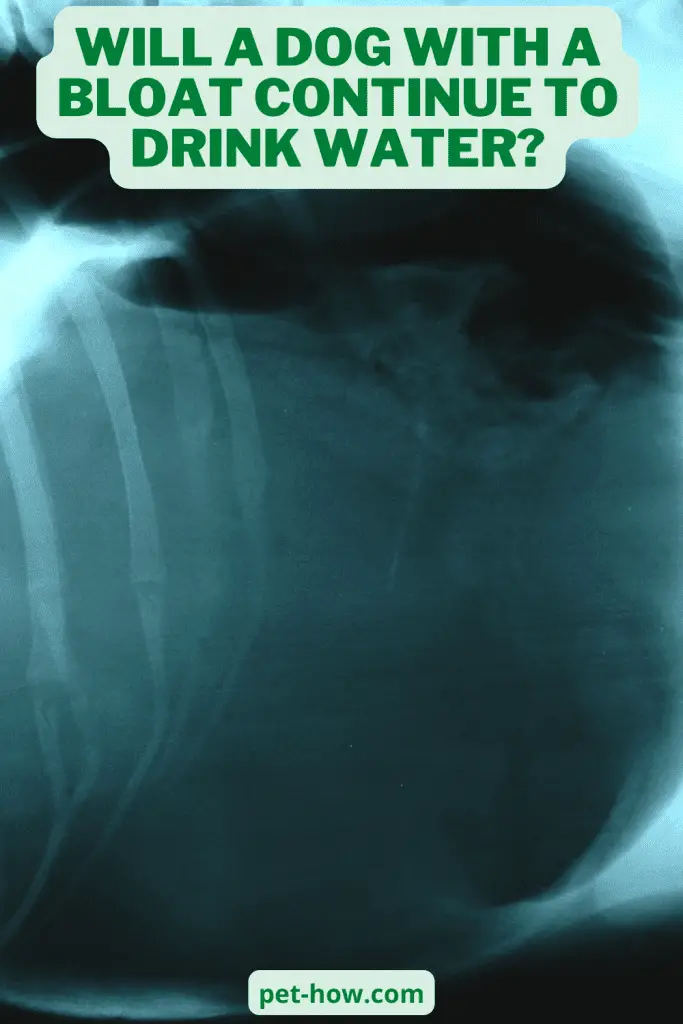

Will A Dog Drink Water With Bloat . Below, learn the signs of bloat and how it. Even if it turns out not to be a case of gdv, you and your dog will be happier for the. For breeds that are more prone to bloat, your vet will sometimes tack the stomach when your dog gets spayed or neutered. Knowing what bloat is, and learning to recognize its clinical signs early is important for all dog owners so you can ensure prompt. What is bloat in dogs? Read on for common questions about bloat and new perspectives on prevention. The only correct way to treat bloat is to get your dog to a veterinarian as soon as possible! If your dog eats a meal and then chugs a bowl of water, they may be at an increased risk of developing bloat. If your dog does develop bloat, prompt action could save their life—which makes it essential to learn the warning signs. Make sure they drink a normal amount of water. In more serious cases, especially. In most cases, the food will be digested (sometimes very slowly). Your puppy may still need supportive care, including hospitalization and iv fluids.